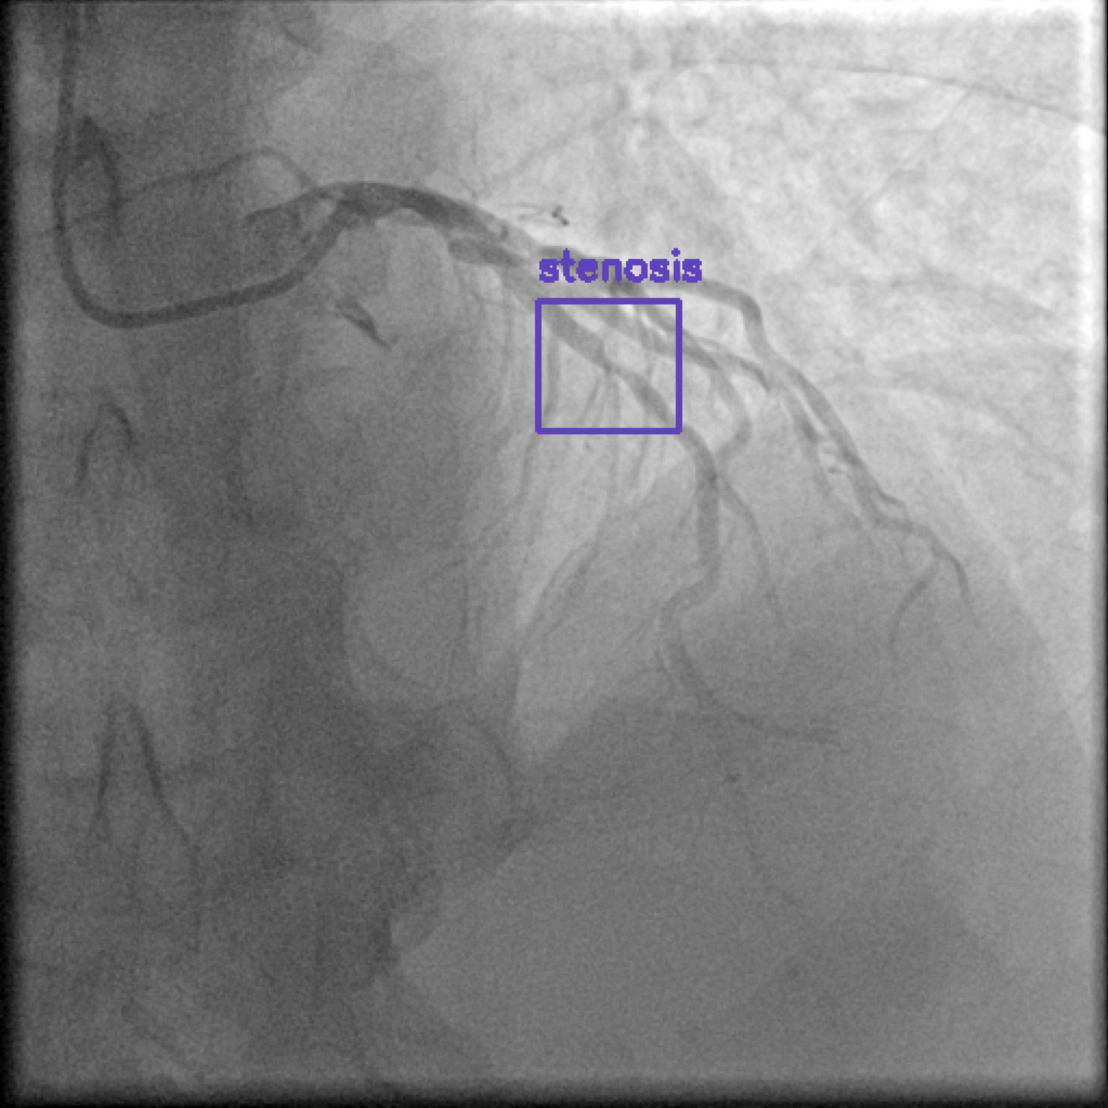

Figure 1 shows sample images from the ARCADE dataset with annotations for stenosis detection. The annotations highlight regions of arterial narrowing, providing ground truth data for training and evaluating object detection models.

To further assess the detection performance, qualitative results for three test images are presented in Figure 2. The first column shows the original images with ground truth annotations. The second, third, and fourth columns depict detections from DINO-DETR, Grounding DINO, and YOLO, respectively.

(a) Original (b) DINO-DETR (c) Grounding DINO (d) YOLO

The qualitative comparison in Figure 2 reinforces the trends observed in the quantitative evaluation. DINO-DETR produced fewer detections, occasionally missing relevant stenotic regions, consistent with its conservative detection strategy aimed at minimizing false positives [6]. Grounding DINO, although capable of identifying more regions, sometimes resulted in cluttered predictions due to over-detections [7]. YOLO provided a reasonable trade-off by effectively capturing anatomical structures while maintaining relatively high confidence scores and clear visualizations [5].